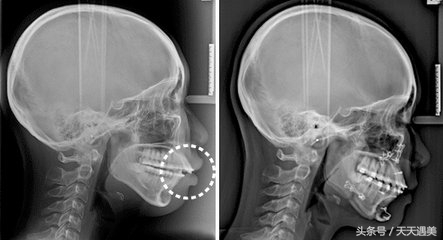

突嘴指的是上下颚同时突出的情况叫做突嘴。很多人都认为突嘴是由于龅牙导致的,其实不然,它是牙颌面畸形的一种,在医学上也叫龅牙凸面型,实际上是因为上颌骨突出,下颌短小后缩造成的突嘴症状。

2.手术 。一般的突嘴手术在医学术用语为:上鄂前部截骨术采用拔掉犬齿后的一颗牙齿,然后截除该部位的牙床骨,整体移动该部位牙床骨和牙齿的方法。